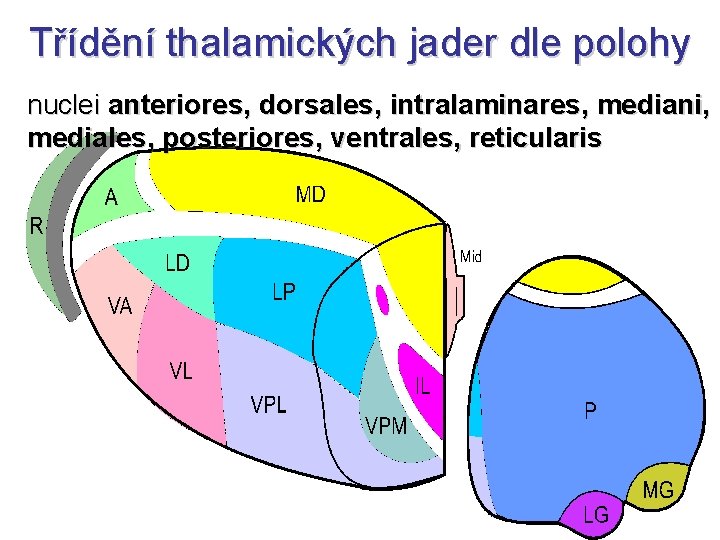

Třídění thalamických jader dle polohy nuclei anteriores, dorsales, intralaminares, mediani, mediales, posteriores, ventrales, reticularis

Specifická jádra • tractus mamillothalamicus ncl. anterior gyrus cinguli – opakované kroužení zesiluje emoce • globus pallidus ncl. VA prefrontální kůra • globus pallidus ncl. VL doplňková motorická kůra • nucleus dentatus cerebelli ncl. VL motorická kůra • lemniscus medialis et spinalis ncl. VPL senzitivní kůra • lemniscus trigeminalis ncl. VPM senzitivní kůra

Asociační jádra • ncl. LD (lat. dors. ) area cingularis posterior • čichový a limbický mozek ncl. MD (mediodors. ) prefrontální kůra (myšlení, úsudek, nálada, stav mysli – integrace se smyslovými podněty) • colliculus superior ncl. LP (lat. post. ) + pulvinar zraková a parietální asociační kůra (přitahuje pozornost k objektům v periferii zrakového pole) • ncll. P (pulvinar) frontální, temporální, parietální a okcipitální asociační kůra (integrace zrakových, sluchových, hmatových a polohových podnětů)

Nespecifická jádra • ncll. intralaminares – pomalá bolest – ARAS • ncll. mediani • limbický systém (dle eferentace)

Ncll. reticulares • GABA • excitační kolaterály ze všech specifických jader talamu a z kůry • inhibiční eferentace zpět do talamu • podobně jako zona incerta • funkce: označuje nové podněty a odlišuje je tak od obvyklých podnětů z prostředí